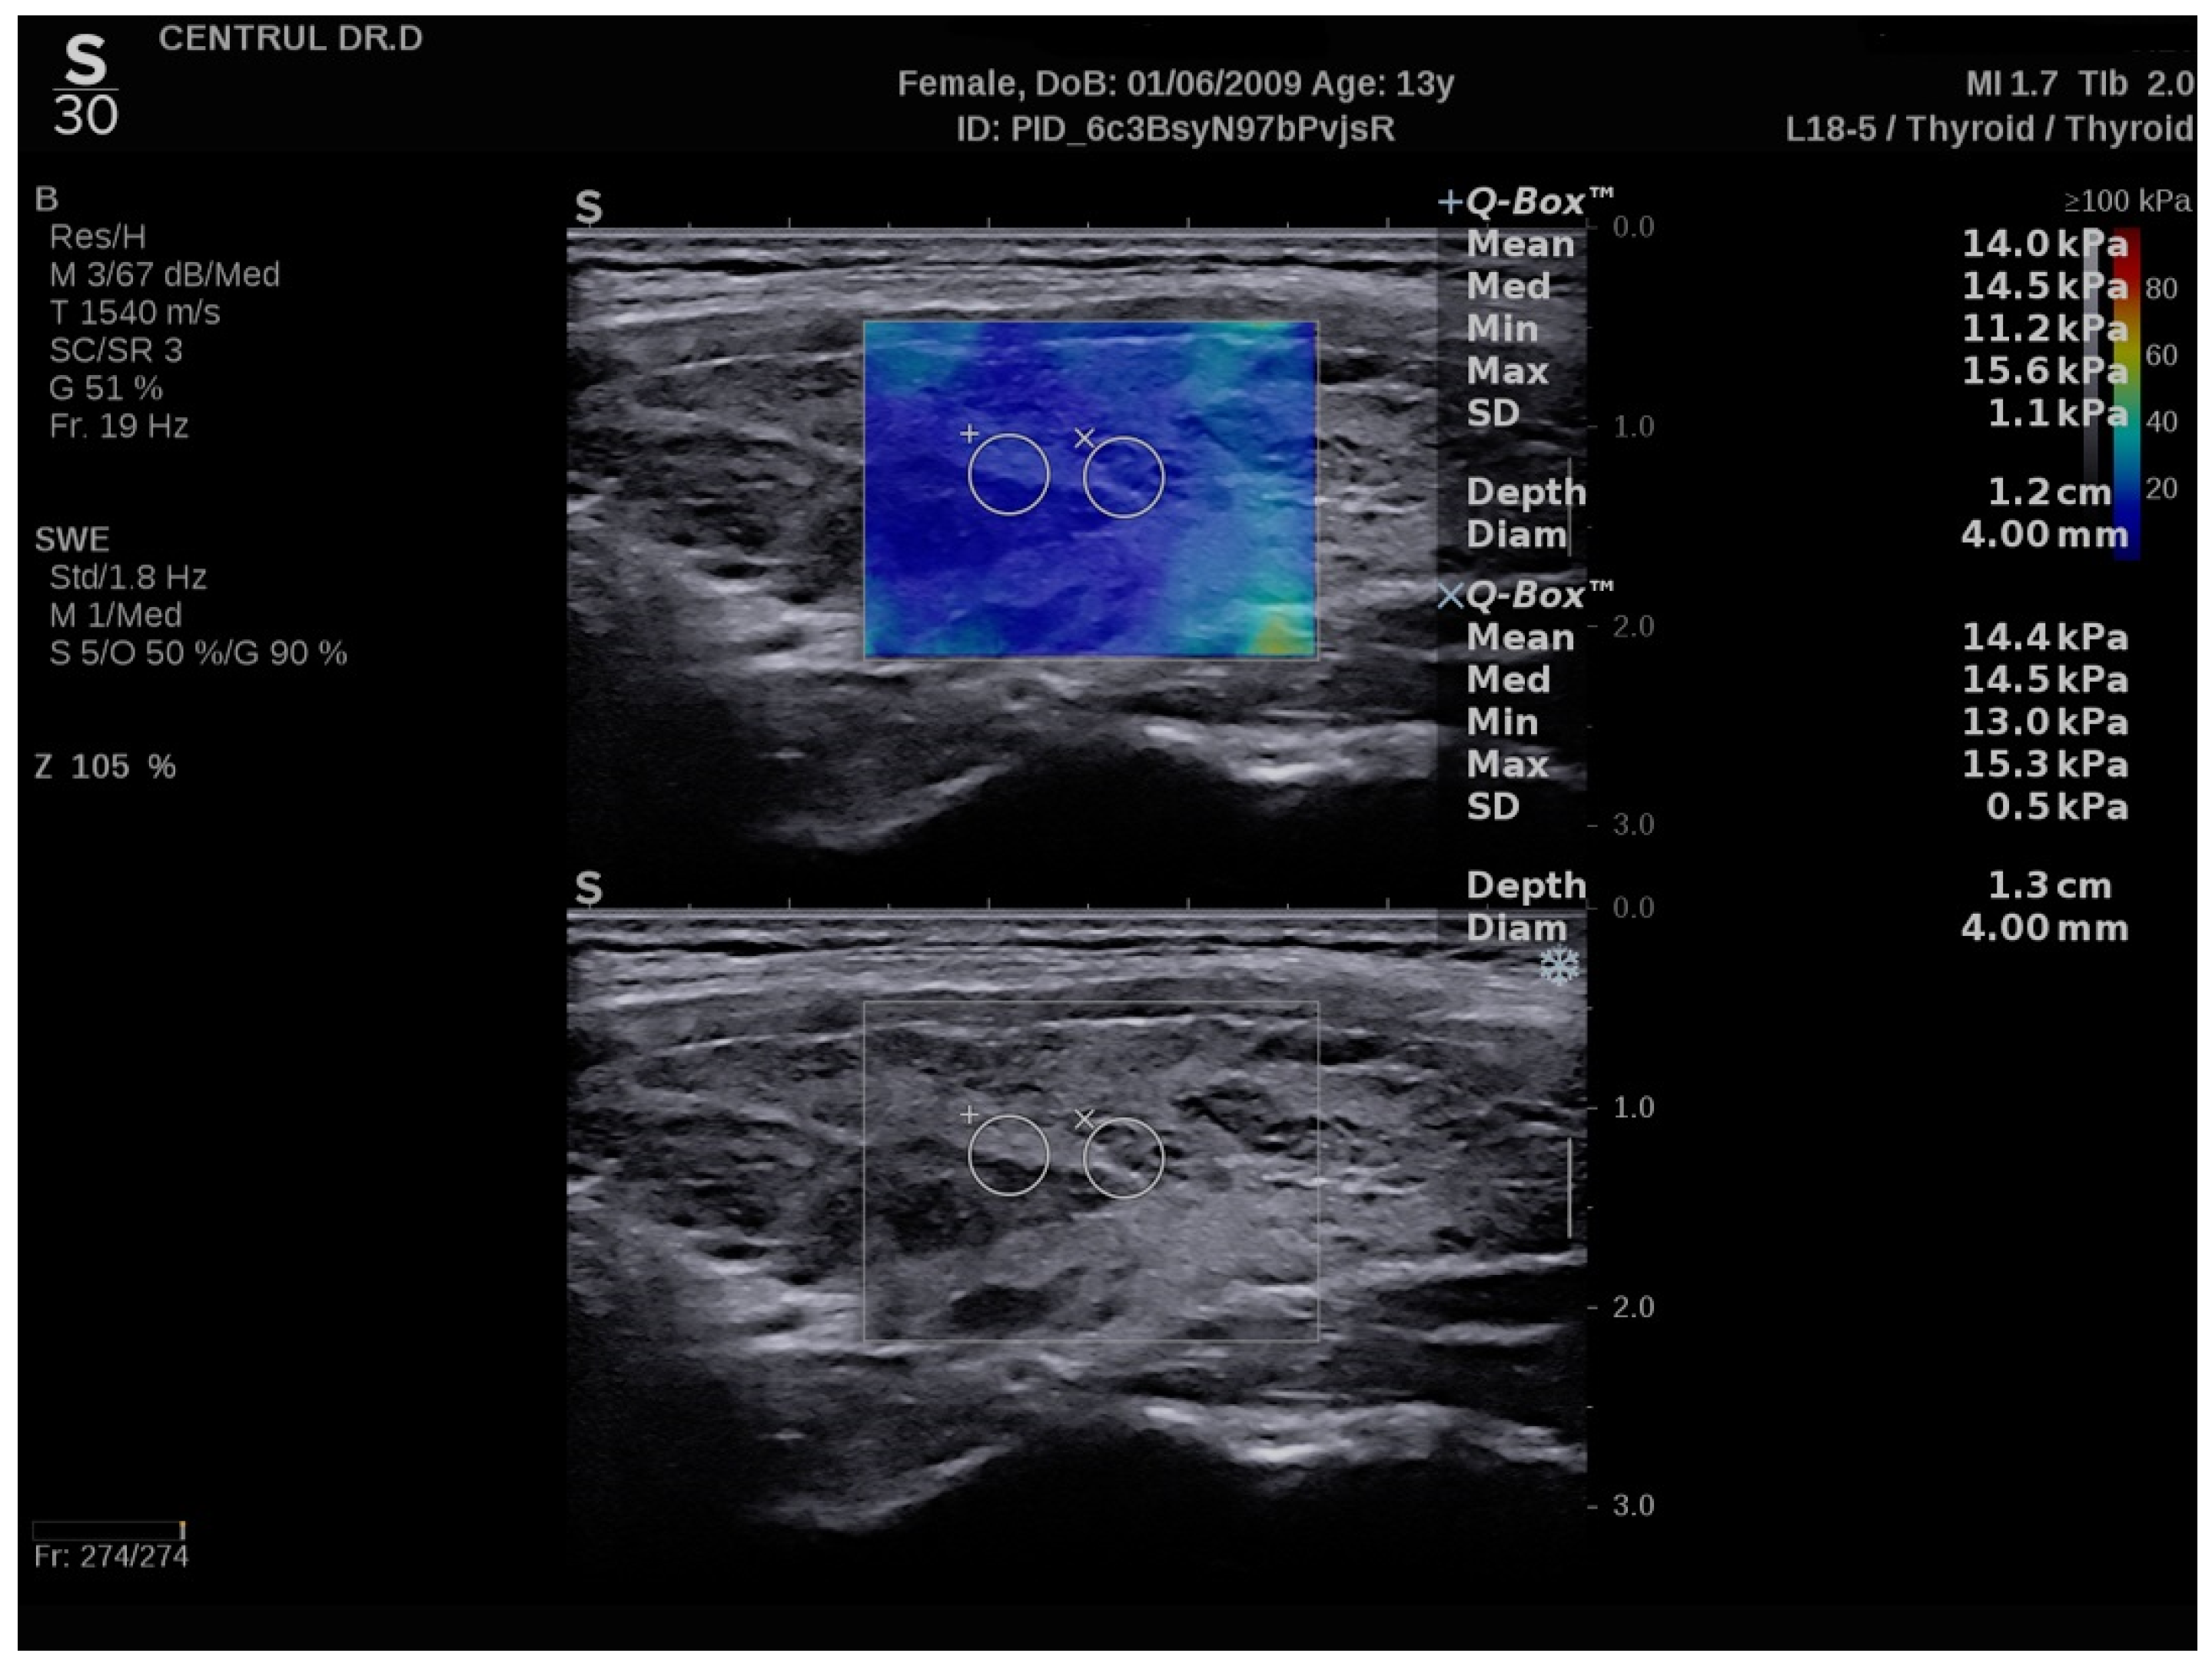

3.2. SWE Measurements

| SWE | Mean EI-THY (kPa) | 13.8 (13.3–17) | 10.1 (9.3–11.2) | <0.0001 |

| Mean EI-LL (kPa) | 13.8 (13.1–17) | 10.4 (9.1–11.2) | <0.0001 | |

| Mean EI-RL (kPa) | 13.9 (13.3–16.6) | 10.2 (9.4–11.1) | <0.0001 | |